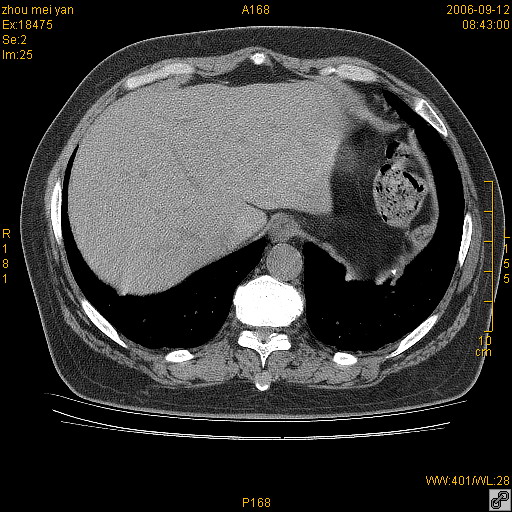

患者、女、55岁。因心率失常住院检查ct发现胸部多发结节。腹部b超肝、胆、胰、脾、肾、子宫附件未见异常。无结核病史,无粉尘接触史。请大家来会诊。谢谢!